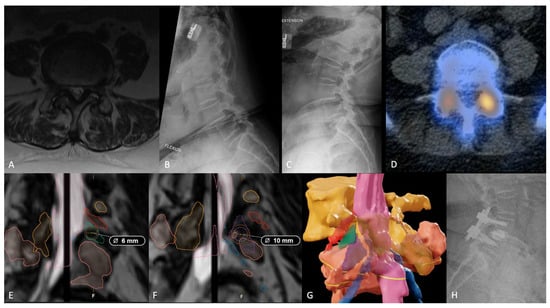

Representative Case

- Tabarestani, T.Q.; Salven, D.S.; Sykes, D.A.W.; Bardeesi, A.M.; Bartlett, A.M.; Wang, T.Y.; Paturu, M.R.; Dibble, C.F.; Shaffrey, C.I.; Ray, W.Z.; et al. Using Novel Segmentation Technology to Define Safe Corridors for Minimally Invasive Posterior Lumbar Interbody Fusion. Oper. Neurosurg. 2023. [Google Scholar] [CrossRef] [PubMed]

- Saeed, M.U.; Dikaios, N.; Dastgir, A.; Ali, G.; Hamid, M.; Hajjej, F. An Automated Deep Learning Approach for Spine Segmentation and Vertebrae Recognition Using Computed Tomography Images. Diagnostics 2023, 13, 2658. [Google Scholar] [CrossRef] [PubMed]